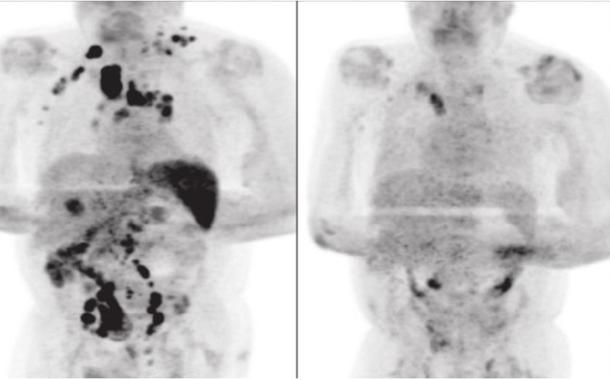

Um homem de 61 anos diagnosticado com de um teve uma remissão do câncer no sistema linfático - o linfoma de Hodgkin -, após contrair o coronavírus